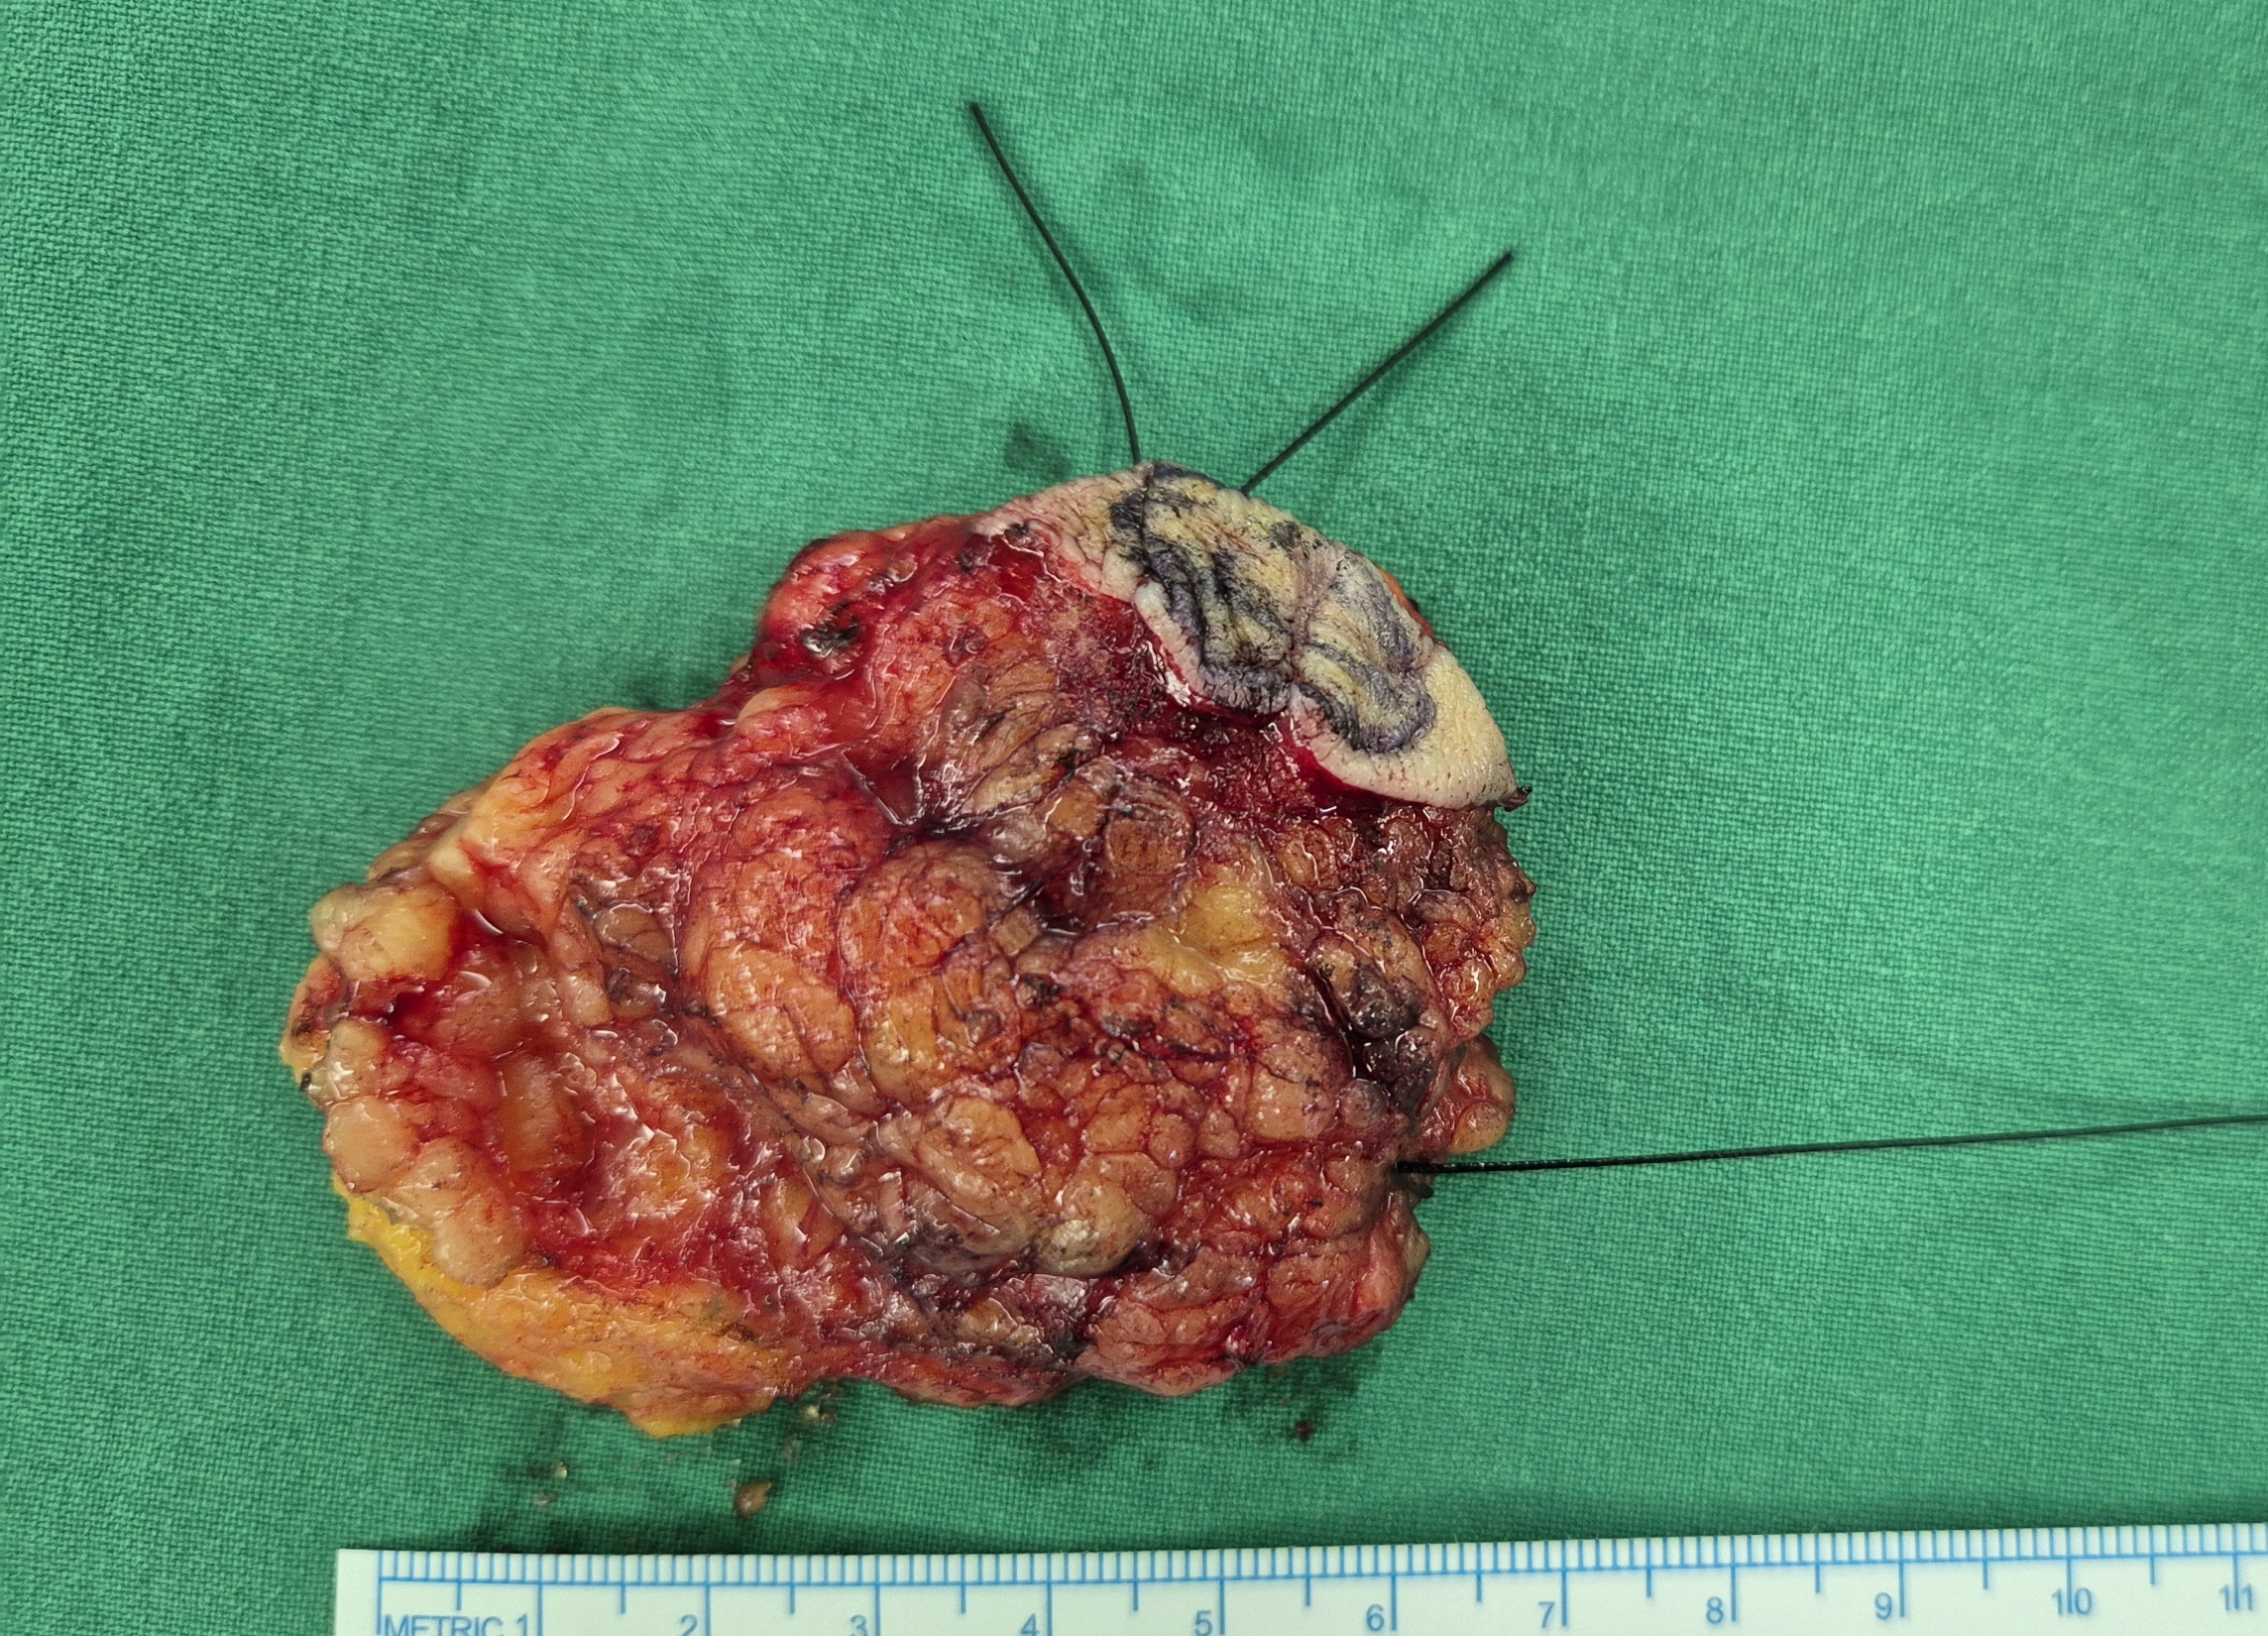

좌측 유방 멍울 주소로 내원하여 총생검상 점액성 침윤암으로 진단된 분입니다.

좌측 유방 부분절제술 및 감시림프절 생검을 시행했습니다.

감시림프절 전이는 없었습니다.

감시림프절.

유방 부분절제.